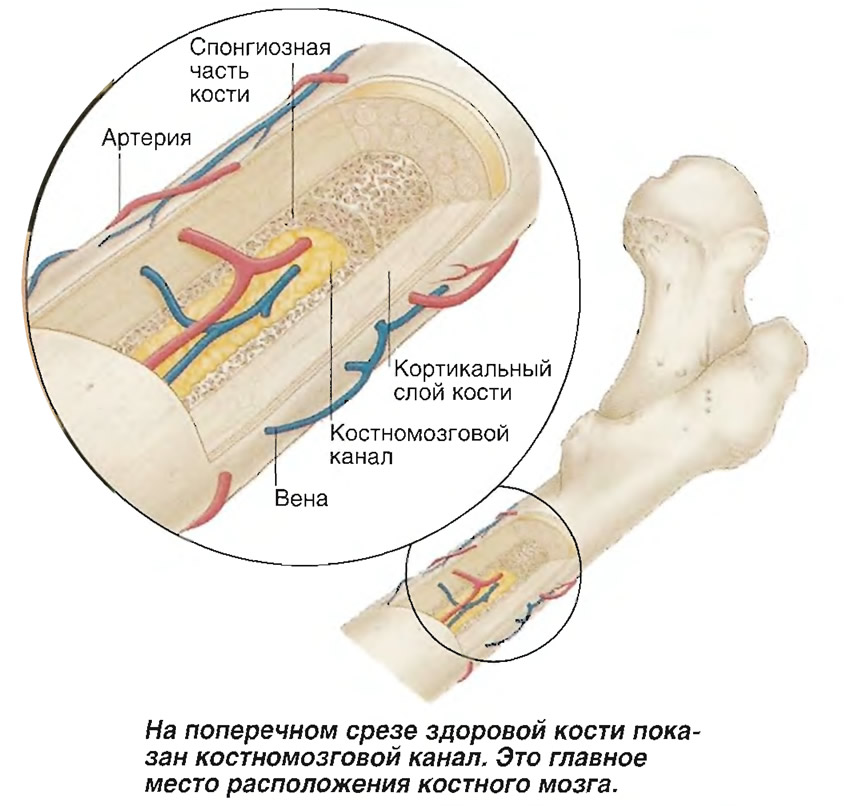

Изучение костного мозга: анатомия и функции